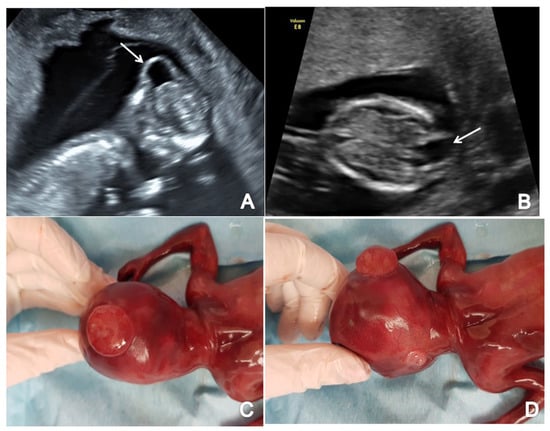

3.2. Cephalocele

The study reports two cases of cephalocele: one located in the occipital region (Figure 5) and one located in the parietal region of the fetal head. Both cases presented with an abnormal calvaria showing the cranial bone defect with a herniated fluid-filled cyst.

Figure 5.

Ultrasound image of occipital cephalocele (the arrow marks the bony defect), diagnosed at 13 weeks + 6 days (Case 13): (A) sagittal view by transvaginal approach; (B) axial view by transabdominal approach; (C,D) specimen presentation after medical TOP.